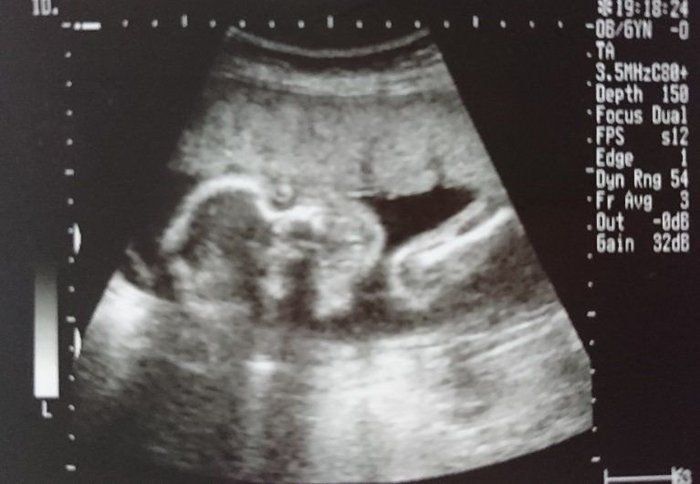

セイコさんの妊娠22週目のエコー写真 初めての4D!感動です

里帰り出産のため、実家の方の病院へ予約に行きました。そちらの病院だと4Dがあるので、初めて見ることができました。すごくリアルで感動です。この子がおなかの中いるのかと、しみじみと愛しく思いました。